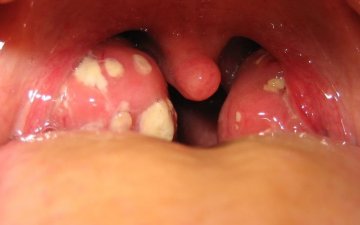

Хоолой мах авахуулсны дараа